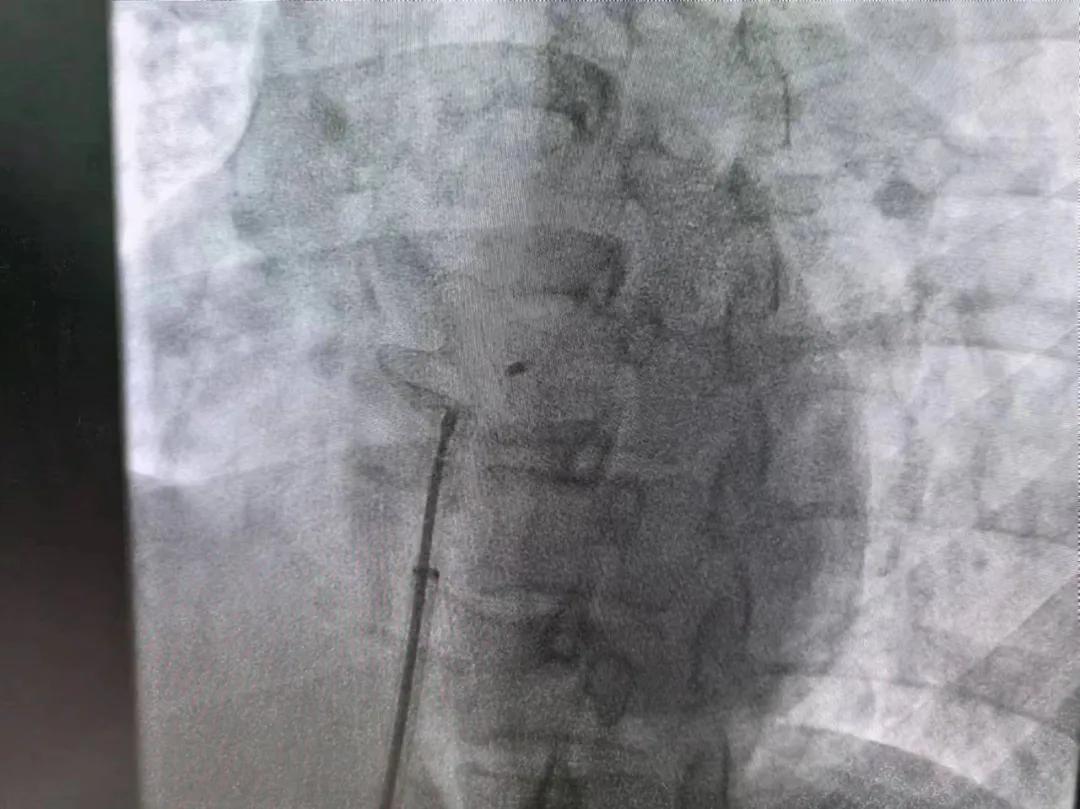

市二院:先天性心臟病介入診療 再創(chuàng)佳績(jī)

繼3月14日市二院成功開展首例卵圓孔未閉介入封堵術(shù)之后,3月21日上午,市二院院長(zhǎng)王瑾及心血管內(nèi)科主任李慧新帶領(lǐng)心血管內(nèi)科介入團(tuán)隊(duì),再次成功為患者實(shí)施“經(jīng)皮房間隔缺損封堵術(shù)”,手術(shù)過程順利。該例病人的成功手術(shù)及康復(fù),標(biāo)志著市二院心血管內(nèi)科在結(jié)構(gòu)性心臟病介入診療中再次達(dá)到了新高度。

患者為中年女性,41歲,近2年一直反復(fù)出現(xiàn)頭暈、頭痛,曾先后在多家醫(yī)院就診。近期患者癥狀加重,出現(xiàn)活動(dòng)后氣喘合并胸悶癥狀,來到心血管內(nèi)科就診。經(jīng)心臟彩超檢查顯示:患者房間隔下段連續(xù)性中斷,缺損直徑達(dá)到了13mm,肺動(dòng)脈壓已經(jīng)輕度增高,確診為房間隔缺損。

于是,院長(zhǎng)王瑾會(huì)診后,詳細(xì)詢問患者病史,認(rèn)真分析臨床癥候群并準(zhǔn)確診斷,耐心做好患者及家屬病情告知和充分溝通。經(jīng)過完善的術(shù)前評(píng)估及準(zhǔn)備,心血管內(nèi)科介入團(tuán)隊(duì)成功為患者實(shí)施“經(jīng)皮房間隔缺損封堵術(shù)”,手術(shù)過程順利。近日,患者已順利康復(fù)出院。 (尹紅婭 潘長(zhǎng)林)